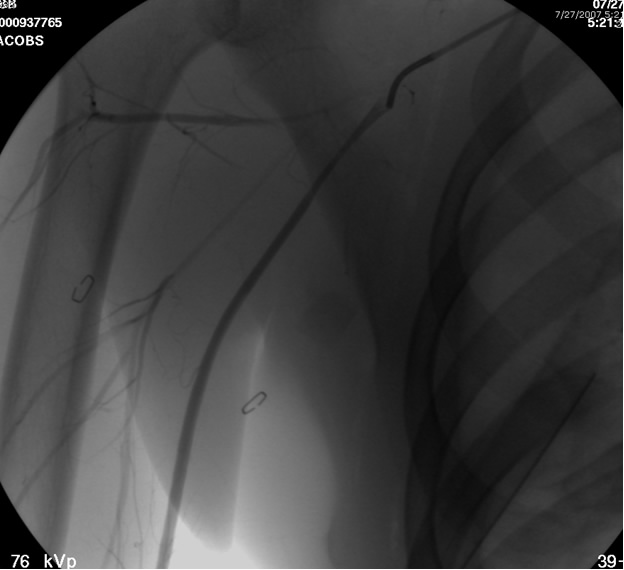

After traversing the vessel with a Glidewire and visualizing the wire conforming to normal arterial profile down into the distal extremity, it is necessary to change out the sheath for a long 8F sheath. It is necessary to advance the sheath into the proximal subclavian artery. To increase support we change out the guide wire for a stiffer Amplatz® (Boston Scientific Corp. Natick, MA) Guidewire extending down into the arm. Next, we perform selective views of the

transected artery visualizing the pseudoaneurysm (Figure 2). A Viabahn covered stent (W.L. Gore & Associates, Flagstaff, AZ) is chosen for the appropriate size of the native vessel being careful not to oversize the stent graft. The stent graft is advanced across the lesion. Selective angiograms through the sheath may be performed to choose correct placement and appropriate landing zones. The stent graft is deployed under fluoroscopic visualization. Next, we utilize an appropriate sized 10 mm low pressure balloon to “iron out the edges” of the stent and bring it up to profile of the artery (Figure 3). Next, completion angiograms are performed to rule out endoleak and complete exclusion of the pseudoaneurysm, as well as to confirm distal runoff to the forearm and palmar branches of the extremity (Figure 4).